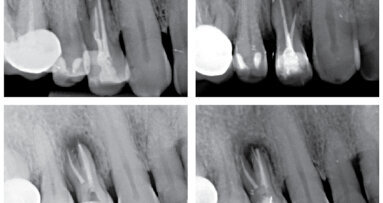

U pacienta v 10 letech byla pro úrazovou ztrátu vitality provedena revaskularizace na zubu 22. Po 2týdenní aplikaci kombinace antibiotik do prostoru pouze chemicky dekontaminovaného kořene byl po vyvolání krvácení aplikován prostředek PRGF a kořen uzavřen pomocí MTA. Zub byl rekonstruován kompozitem. Na kontrole po 5 letech je viditelně zvětšený objem tkáně kořene a absence projasnění. (Obr. 4–6)

Častou komplikací (téměř inherentní součástí) tohoto ošetření je zbarvení korunek ošetřených zubů, které je následně po vytvoření kořenové tkáně nutno řešit vnitřním bělením (obr. 7).